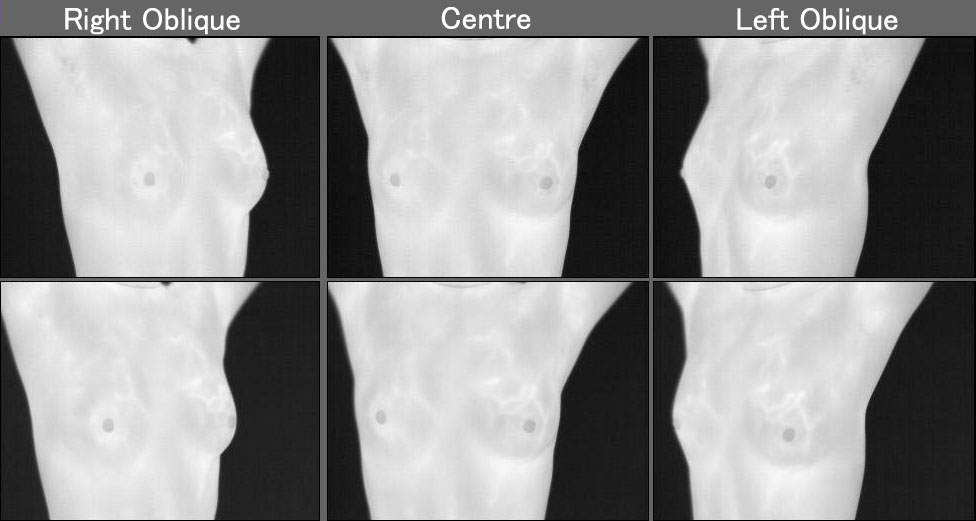

Patient B:

Patient identified by thermogram as having highest thermobiological risk on the right central breast, associated with signs of infiltrative cancer.

Gray-Scale Image